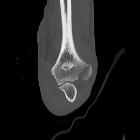

Epicondyle fracture (elbow)

Epicondyle fractures are common injuries in children. They represent 10% of all elbow fractures in children and usually occur in boys after a fall on an outstretched arm.

Medial epicondyle fractures comprise most of these injuries. They can usually be treated with splinting and early physiotherapy. However, operative management is required in cases where there is a displaced fragment, where the fracture is open, or where there is ulnar nerve disruption.

Lateral epicondyle fractures are far less common and much less likely to require operative management.